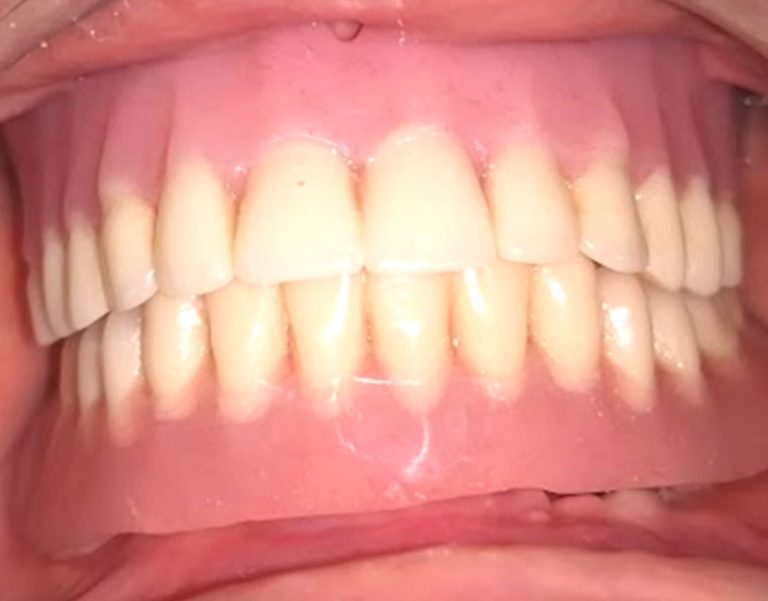

Protesis total sobre implantes

ODONTOLOGIA ESTETICA